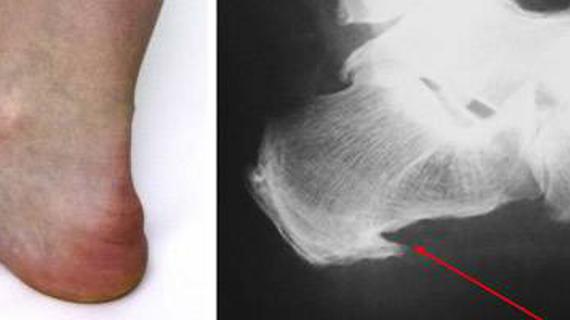

Плоскостопие - МКБ-10 код рассматривает как М21.0, М21.4 и Q66. 5 в зависимости от разновидности - является довольно распространенным заболеванием, при котором...